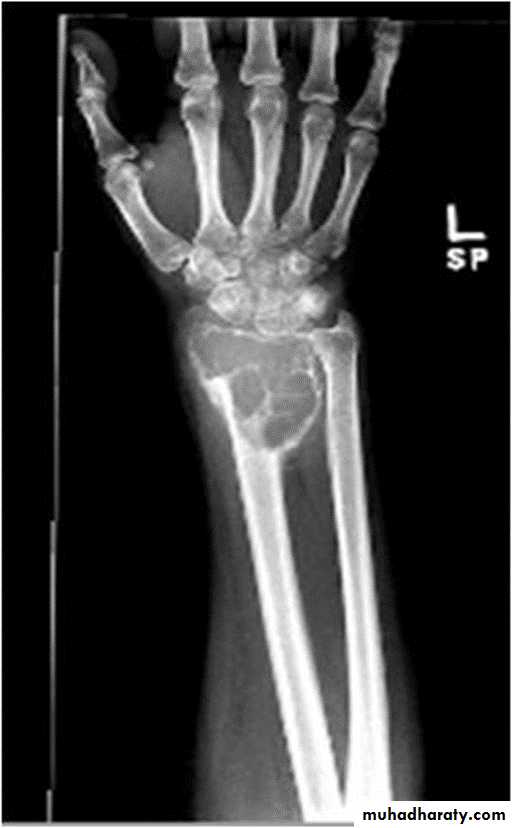

Subperiosteal bone resorption seen particularly in the radial aspect of the middle phalange (hyper parathyriodism)

Sub periosteal resorption at the radial aspect of the middle phalanges (hyper parathyriodism ).